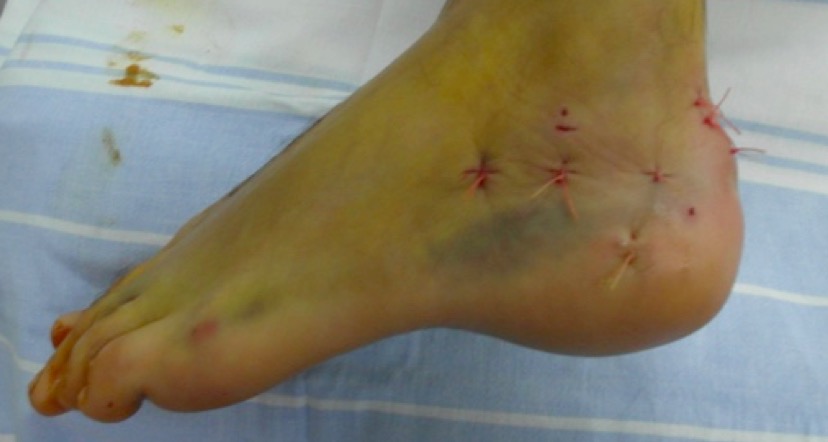

Фото. 2 дня отделяемого нет. Получает по 1,0 гр ванкомицин 3 раза в день. Местно перевязки с бетадином.

Спасибо за активное обсуждение. Прооперировали 2 недели назад с пластиной LCP и винтами, Chronos. Заживление проблемное. Сохраняется скудное серозное отделяемое. Швы сегодня сняли. По техническим причинам не получается выложить послеоперационные снимки. Как только, так сразу выложу.

В отделении ранее активно применялся накостный остеосинтез переломов пяточной кости. Про шкалу Андрея Анатольевича Волны (ABCDEF) мы тогда не знали (думаю, что могли бы иметь меньшее количество осложнений). Но осложнений было много. Частая причина – краевые некрозы кожных лоскутов и подлоскутные гематомы. Мало привлекательно, когда после снятия швов из раны длительно подбегает серозная жидкость или видна пластина.